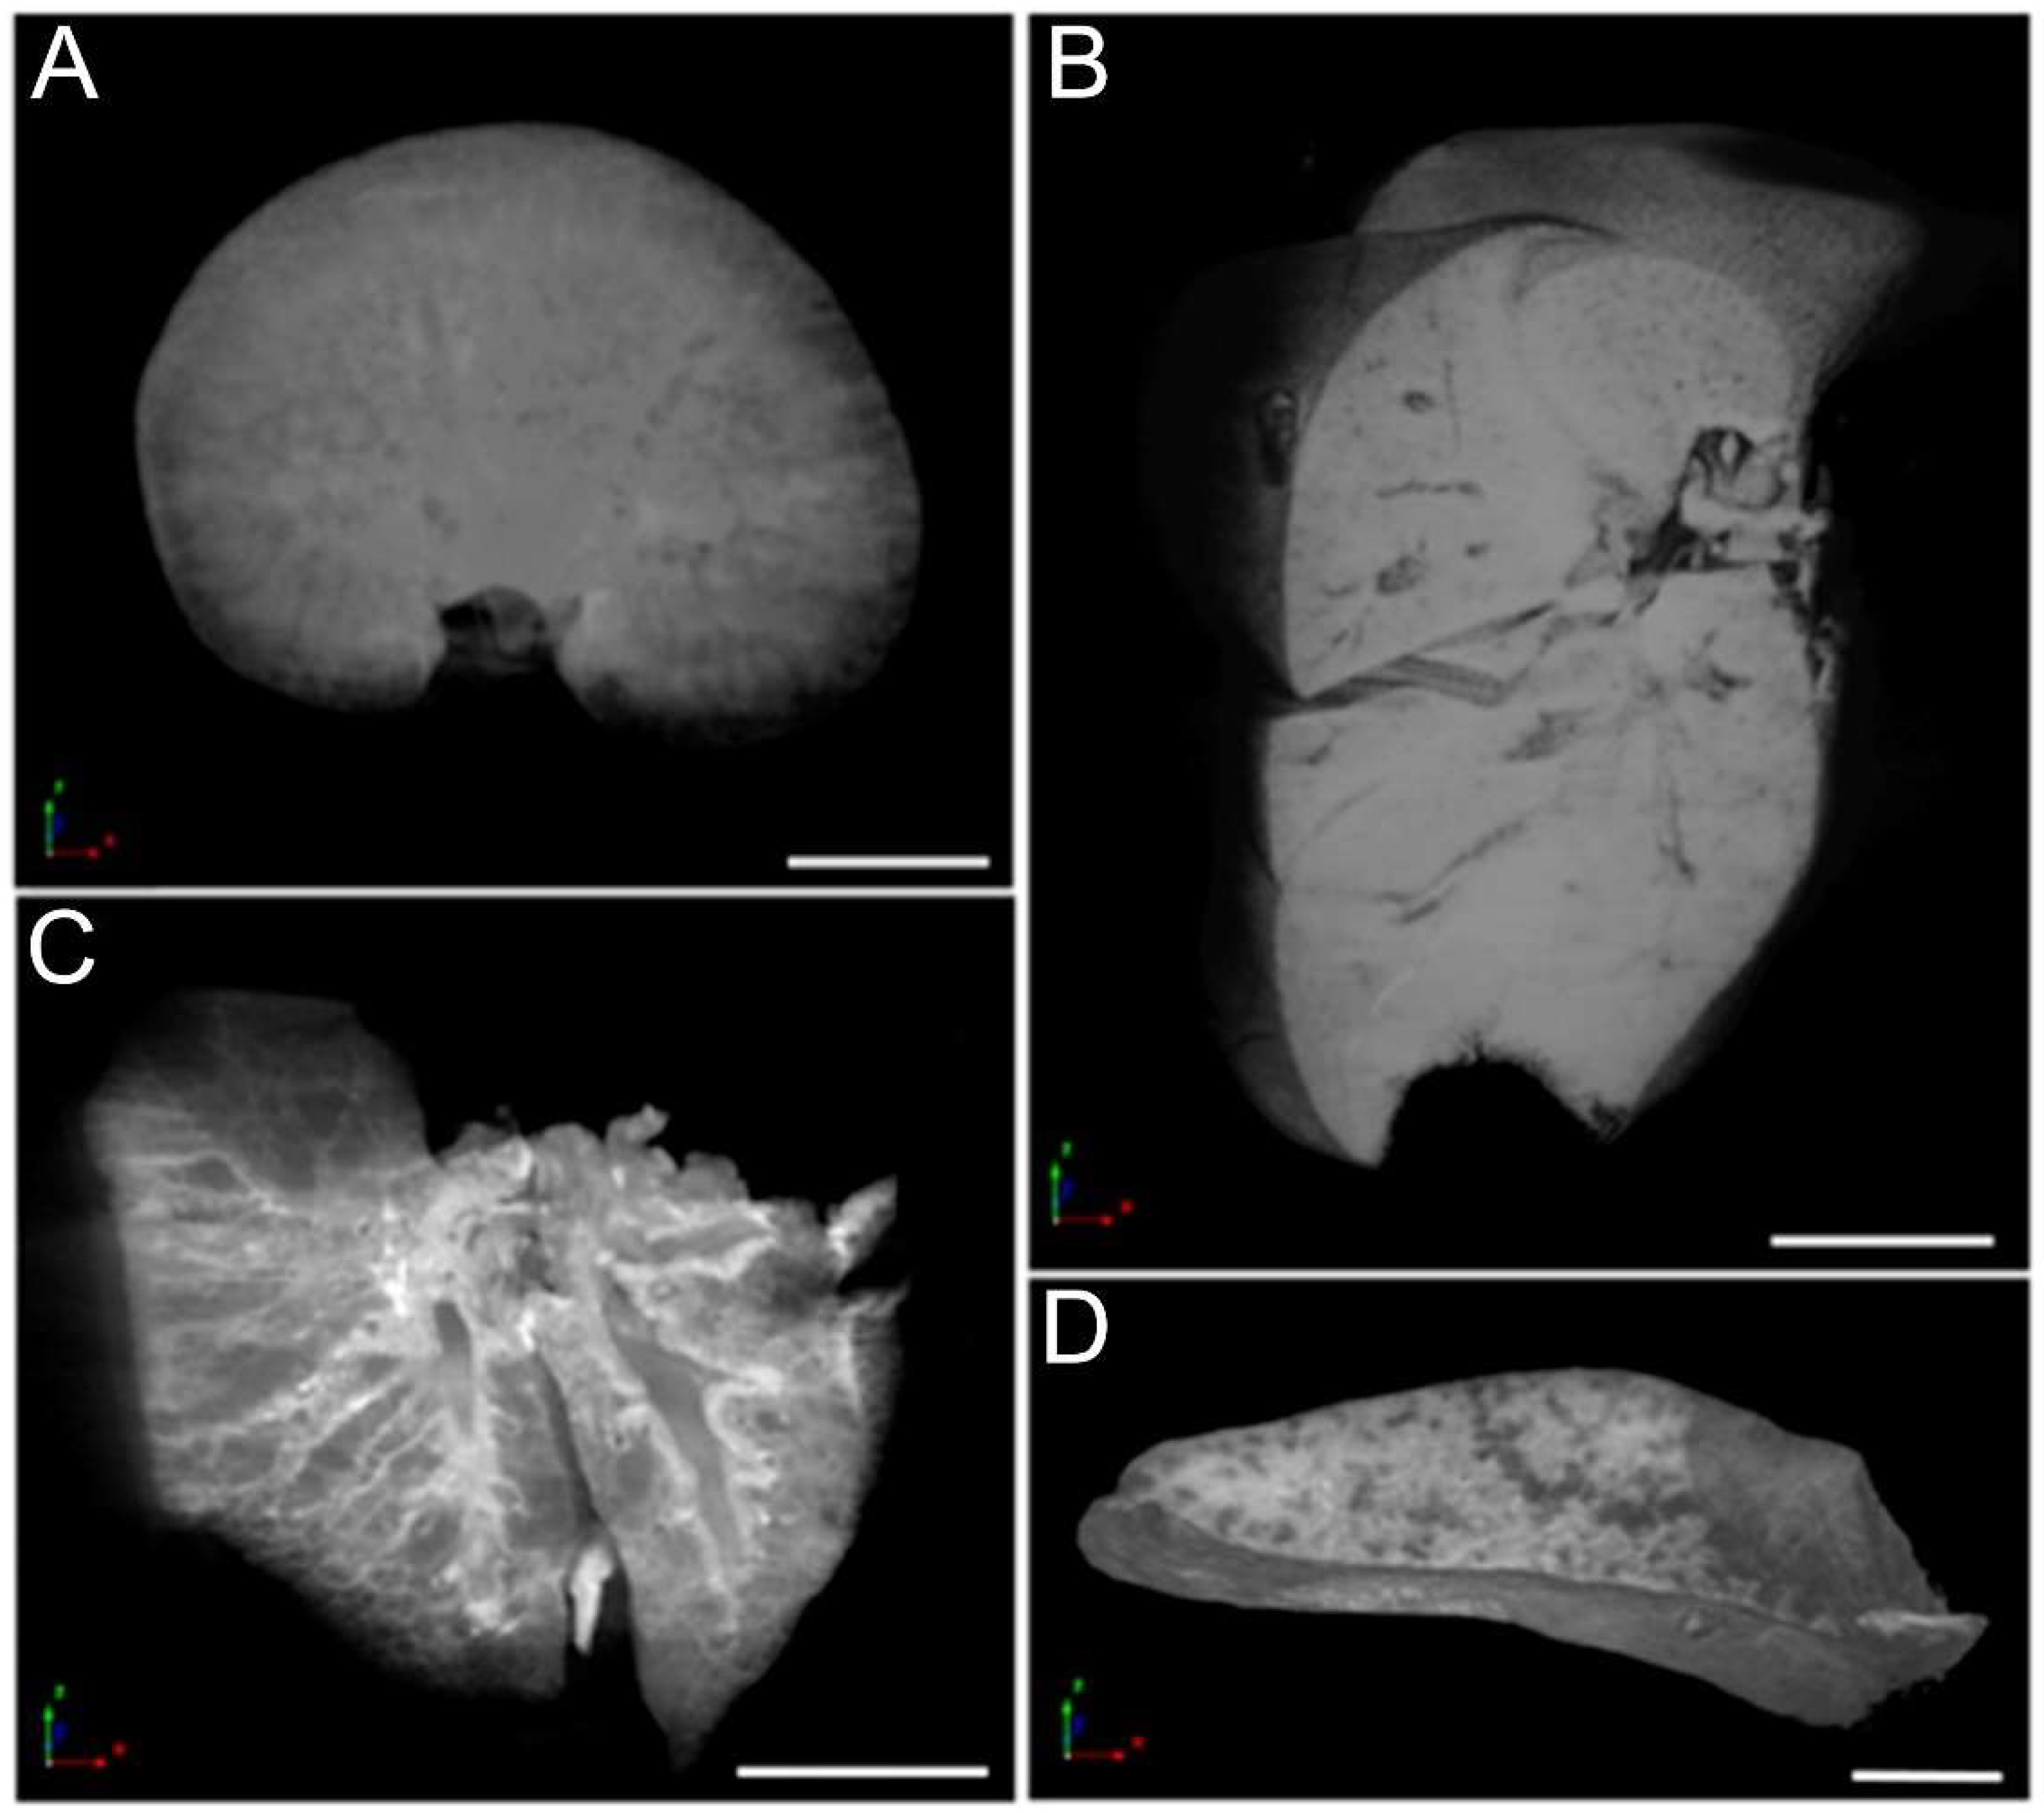

2.7. Organ Micro-Computed Tomography (Micro-CT) and Histological Analysis

3.6. Micro-CT Analysis